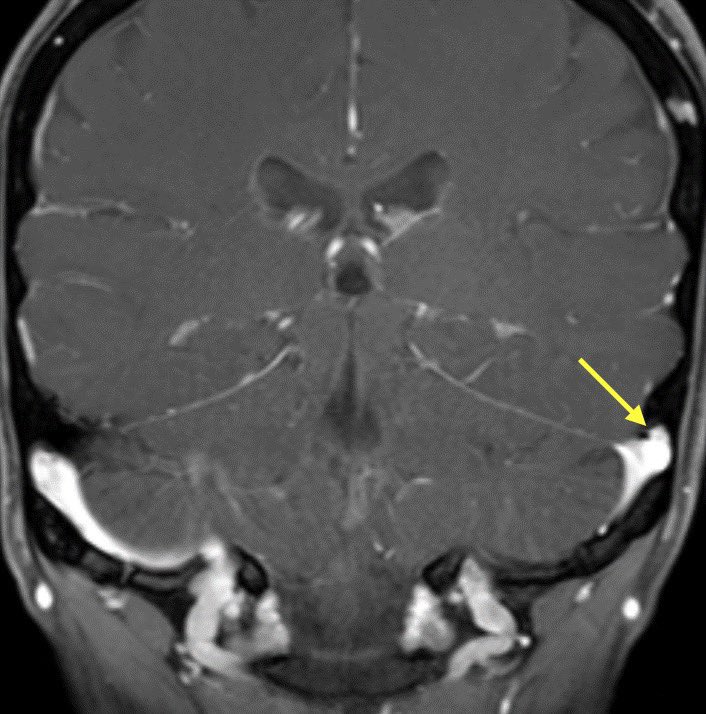

🔷TRANSVERSE SINUS STENOSIS & IDIOPATHIC INTRACRANIAL HYPERTENSION

🔸Intrinsic and extrinsic causes

INTRINSIC: Typically arachnoid granulations

🔹Arachnoid granulations may be incidental though they can produce IIH when obstructing a dominant transverse sinus or simultaneously blocking both

🔹Look for a round/lobulated filling defect with CSF signal on all images

EXTRINSIC: Defined as luminal narrowing with obtuse margins

🔹Typical cause of extrinsic stenosis is IIH though can occur without signs of IIH

💡Bilateral transverse sinus stenosis is seen in 94% of patients with lIH

💡 Stent placement is safe and effective in patients with transverse sinus stenosis (w/ or w/o lIH)